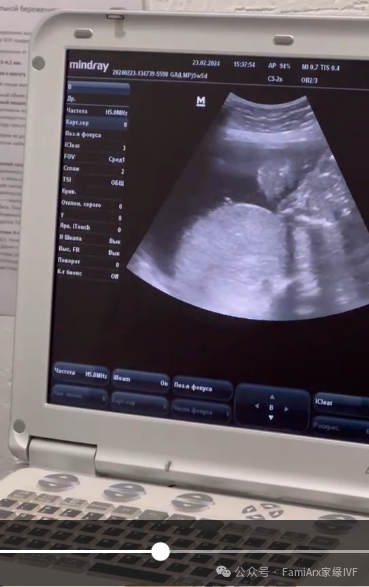

然后2月23日最新的产检时候,我们看到成型的小宝宝在吃自己的小手指。一切非常健康。